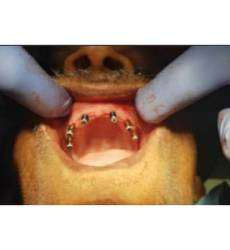

CTARS IPS has a custom made software which can able to guide an implantologist to place an implant in a predetermined surgical plan which will be more precise and accurate to the deep insight about patient anatomy and also helps in reducing the time duration and increasing patient comfort.No two patients teeth are the same. That’s why each and every CTARS IPS guide is custom made to fit your implant plan and patient’s anatomy.CTARS is available with tooth or bone (dentulous or edentulous) supported.

Pilot Drill Guided